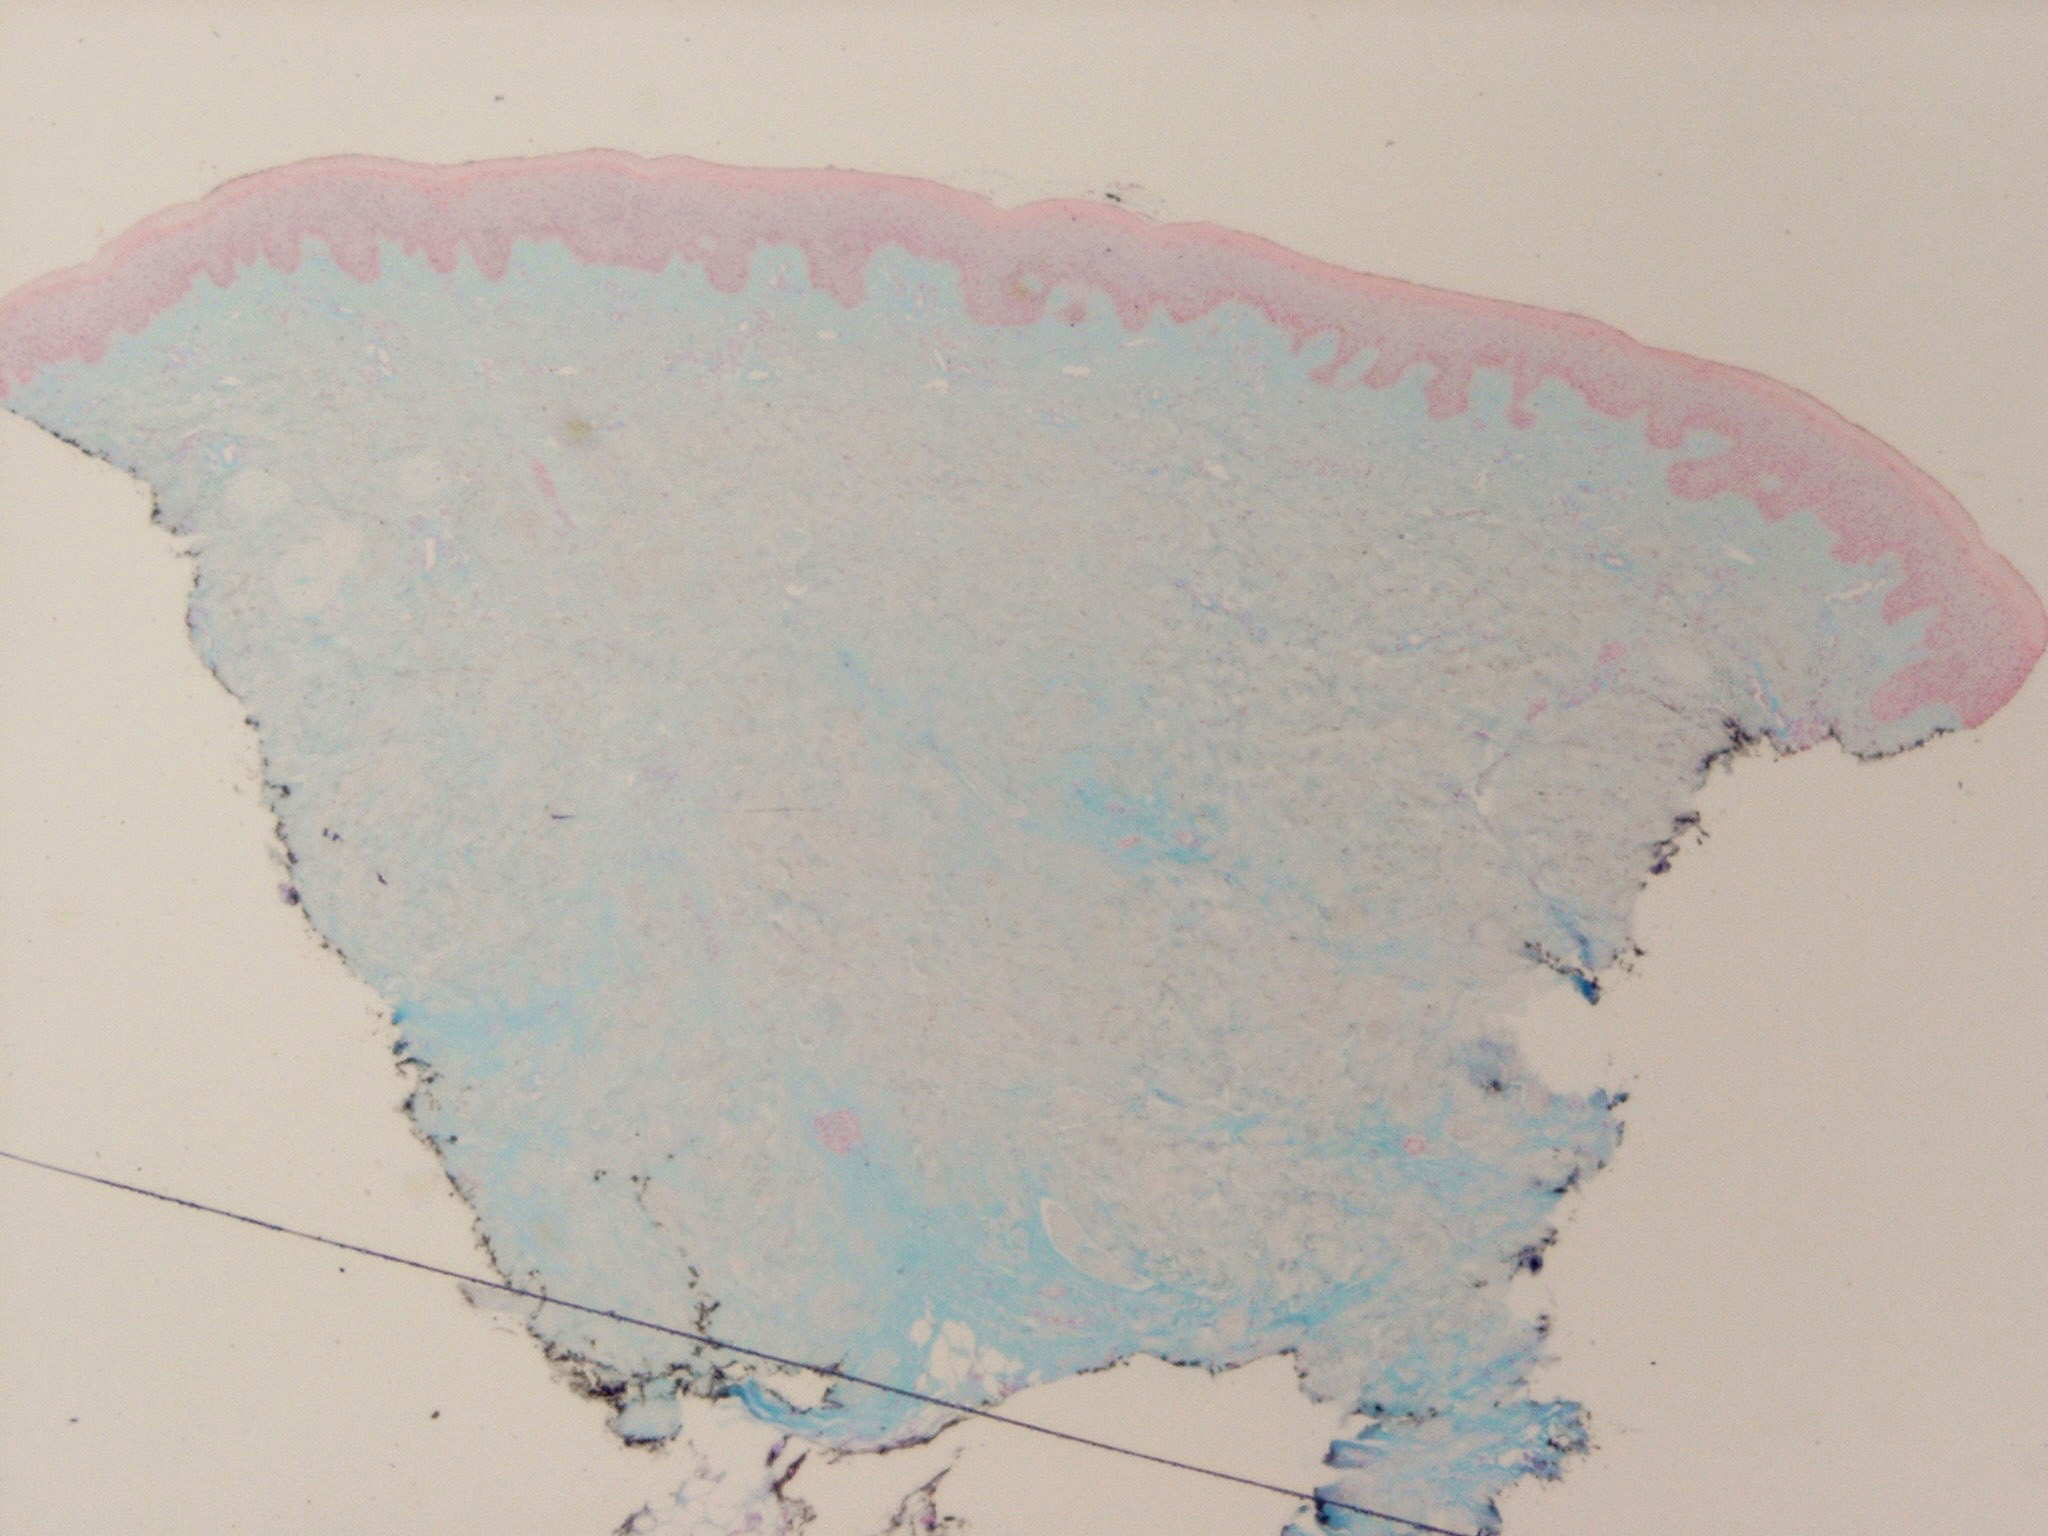

morphea